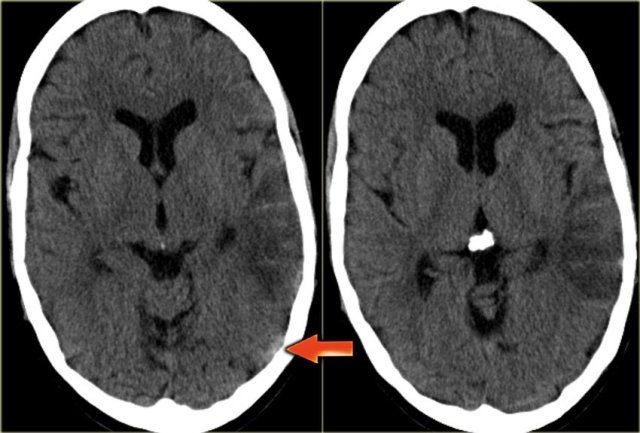

Venous infarction (4) - Deep cerebral veins

On the far left a FLAIR image demonstrating high signal in the left thalamus.

When you look closely and you may have to enlarge the image to appreciate this, there is also high signal in the basal ganglia on the right.

These bilateral findings should raise the suspicion of deep cerebral venous thrombosis.

A sagittal CT reconstruction demonstrates a filling defect in the straight sinus and the vein of Galen (arrows).

On the left a young patient with bilateral abnormalities in the region of the basal ganglia.

Based on the imaging findings there is a broad differential including small vessel disease, demyelinisation, intoxication and metabolic disorders.

Continue with the T1-weighted images in this patient.

Notice the abnormal high signal in the internal cerebral veins and straight sinus on the T1-weighted images, where there should be a low signal due to flow void.

This was unlike the low signal in other sinuses.

The diagnosis is bilateral infarctions in the basal ganglia due to deep cerebral venous thrombosis.